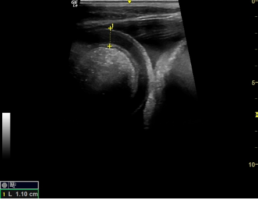

Wandverdickter Dünndarm mit Messung der Wanddicke (Norm bis 4mm)